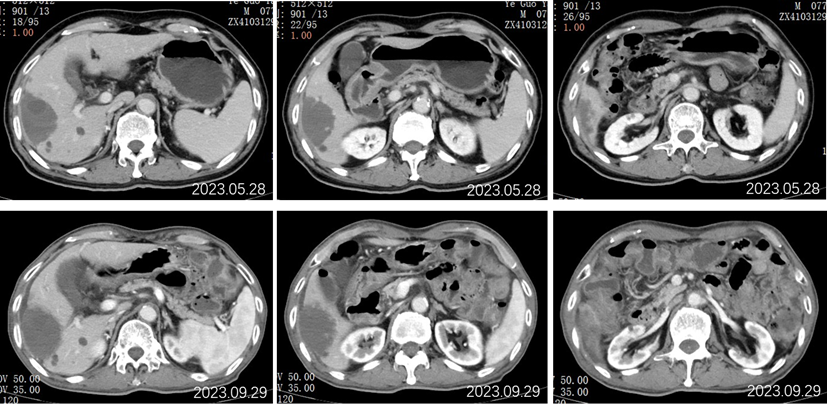

2022.09.27腹部CT增强:肝胆管细胞癌治疗后复查:1、肝右叶多发占位,较前大小相仿,目前仍可见活性;2、肝内及双肾多发小囊肿,相仿;肝S2段小血管瘤考虑,相仿;3、慢性胆囊炎改变;4、肝内钙化灶;前列腺钙化灶。

2022.11.25腹部CT增强:肝胆管细胞癌治疗后复查:对比2022-09-27日:1、肝右叶多发占位,较前大小相仿,目前仍可见活性;2、肝内及双肾多发小囊肿,相仿;肝S2段小血管瘤考虑,相仿;3、慢性胆囊炎改变;4、肝内钙化灶;前列腺钙化灶。

2023.5.28腹部CT增强:肝胆管细胞癌治疗后复查:对比2022-11-25日:1、肝右叶多发占位,较前相仿;2、肝内及双肾多发小囊肿,肝S2小血管瘤,大致相仿;3、慢性胆囊炎改变;胆囊内点状结石未见显示;4、肝内钙化灶;前列腺钙化灶。

2023.09.29腹部增强CT:肝胆管细胞癌治疗后复查:对比2023-05-28日:1、肝右叶多发占位,较前大致相仿;2、肝内及双肾多发小囊肿,肝S2小血管瘤,大致相仿;3、慢性胆囊炎改变;胆囊周围渗出,较前稍增多;4、肝内钙化灶;前列腺钙化灶;新见盆腔少量积液。